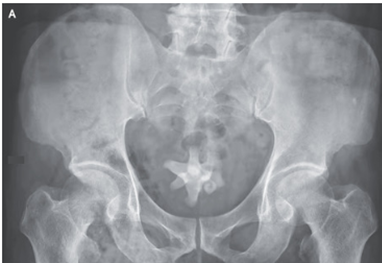

13歳少年。アフリカ出身。集団検診にて肉眼的血尿を認め、精査目的に小児科受診。 身体所見では発熱や側腹部痛や排尿障害がないことを含め全て正常だった。 尿検査では…